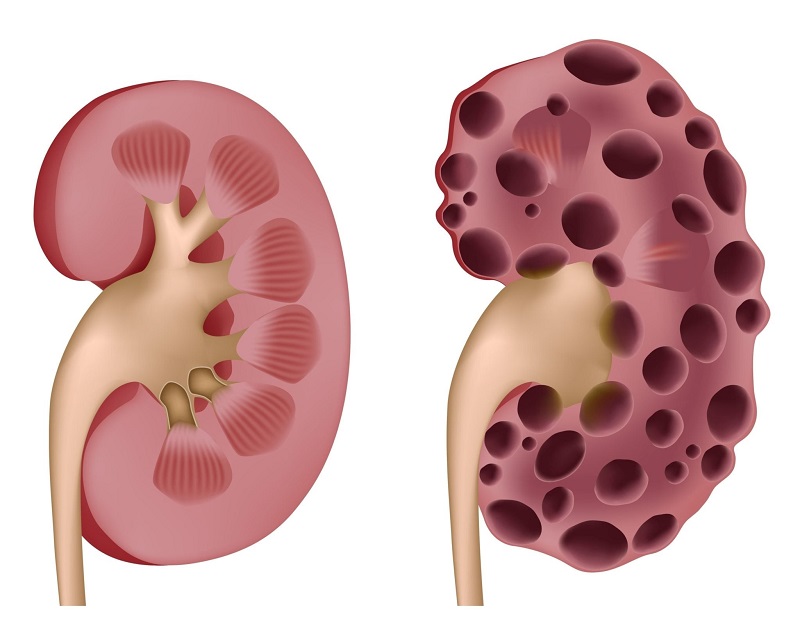

کیستهای کلیه (کیستهای کلیوی) کیسههای کوچک و گردی هستند که دارای دیواره نازکی بوده و حاوی مایع آبکی هستند.این کیستها میتوانند بروی سطح کلیه یا داخل ساختارهای کلیه به نام نفرونها تشکیل شوند.

اندازه کیستهای کلیه متفاوت است، اما بیشتر آنها کمتر از 5 سانتی متر قطر دارند و ممکن است با گذر زمان رشد کنند یا تغییری در اندازه نداشته باشند.برخی افراد ممکن است فقط یک کیست داشته باشند در حالیکه ممکن است در سایرین این کیستها متعدد باشند

کیستهای کلیه میتوانند در یک یا هر دو کلیه تشکیل شوند.کیستهای ساده کلیه معمولاً عملکرد کلیهها را تحت تأثیر قرار نمیدهند و اغلب نگران کننده نیستند. در موارد نادر، یک کیست بزرگ ممکن است باعث ایجاد درد شود. در چنین شرایطی، پزشک ممکن است کیست را تحت نظر داشته باشد. در مواردی که کیست مشکوک به نظر میرسد، آزمایشهای اضافی یا حذف کیست توصیه میشود.

کیست های ساده کلیوی بر اساس نمای ظاهری خود در سی تی اسکن به ٤ درجه تقسیم می شوند: